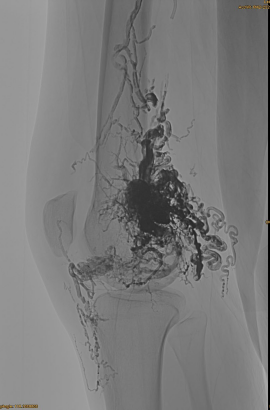

Основна информация на пациента: женска, 36 години; AVM Pelvis, Hip, Knee, Left OSG, множество pre - емболизации.

Използвани продукти: 3PCS LAVA-34,14PCS LAVA-18.

Първоначален DSA:

Краен резултат:

Едва ли някакъв венозен отток:

Късна фаза, друг Ембо е необходим, но много по -добре: